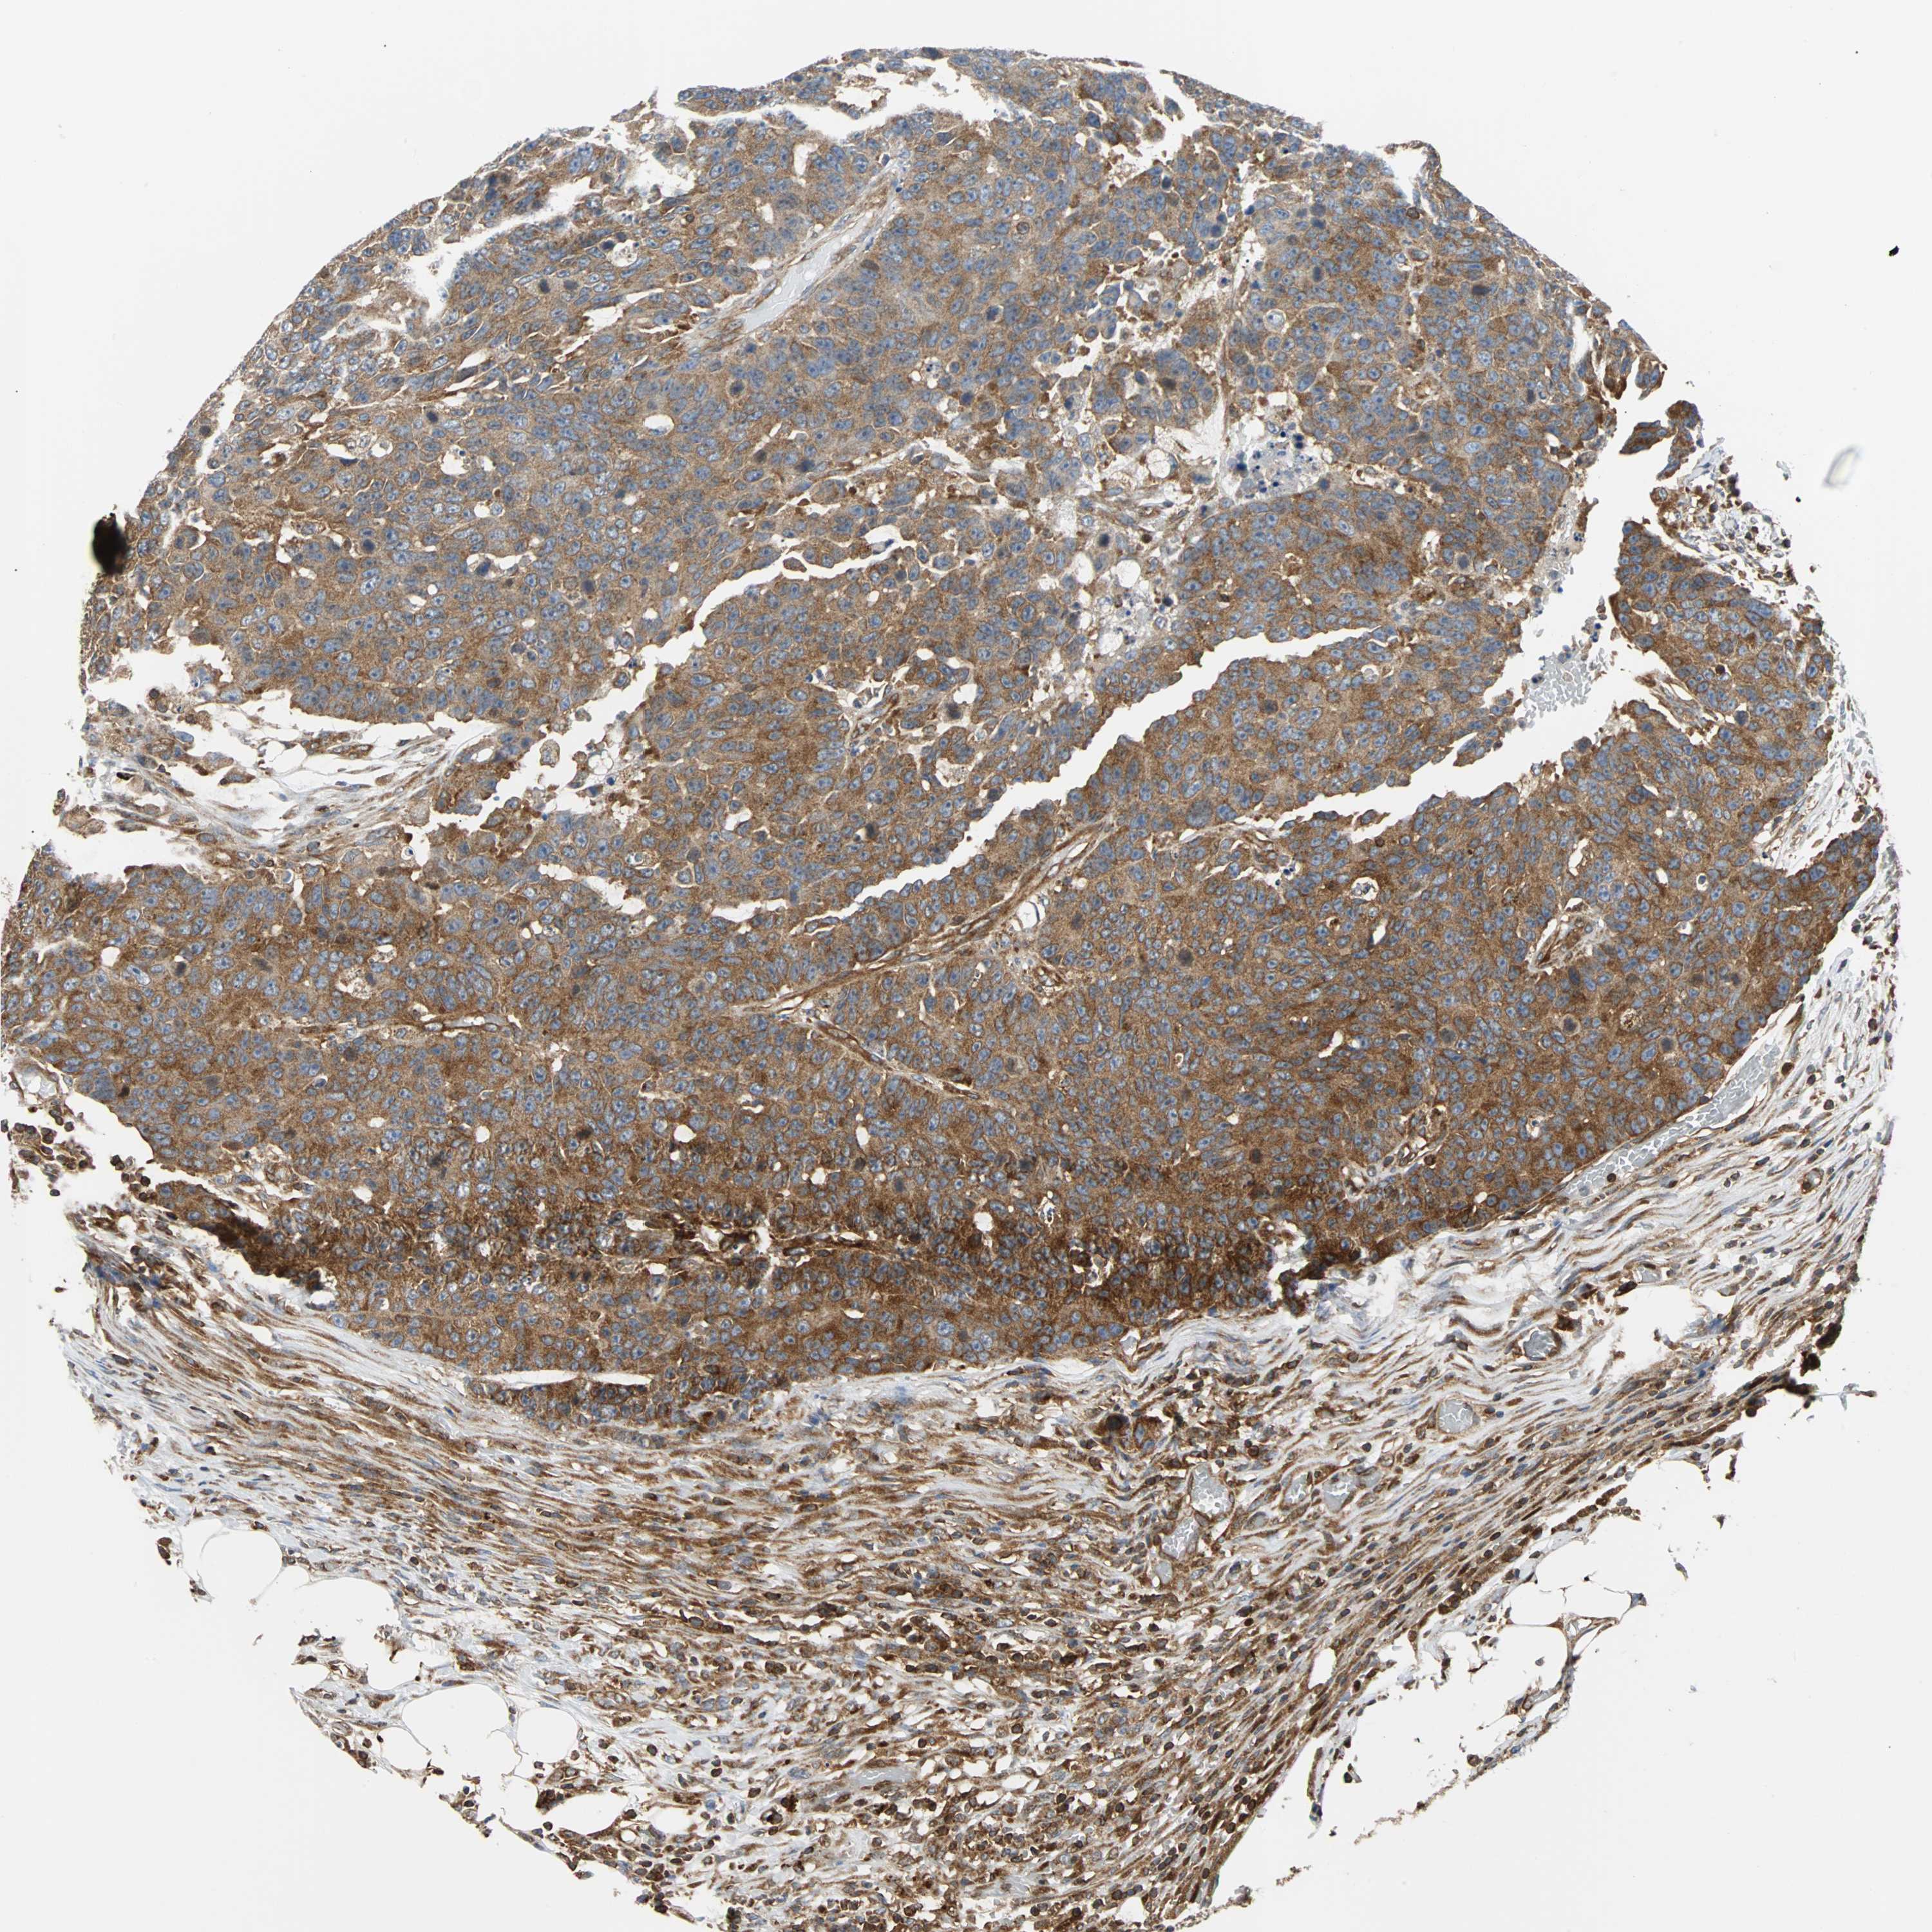

CANCER COLORECTAL CANCER Show tissue menu

Colorectal cancer

Human cancer

Colon adenocarcinoma